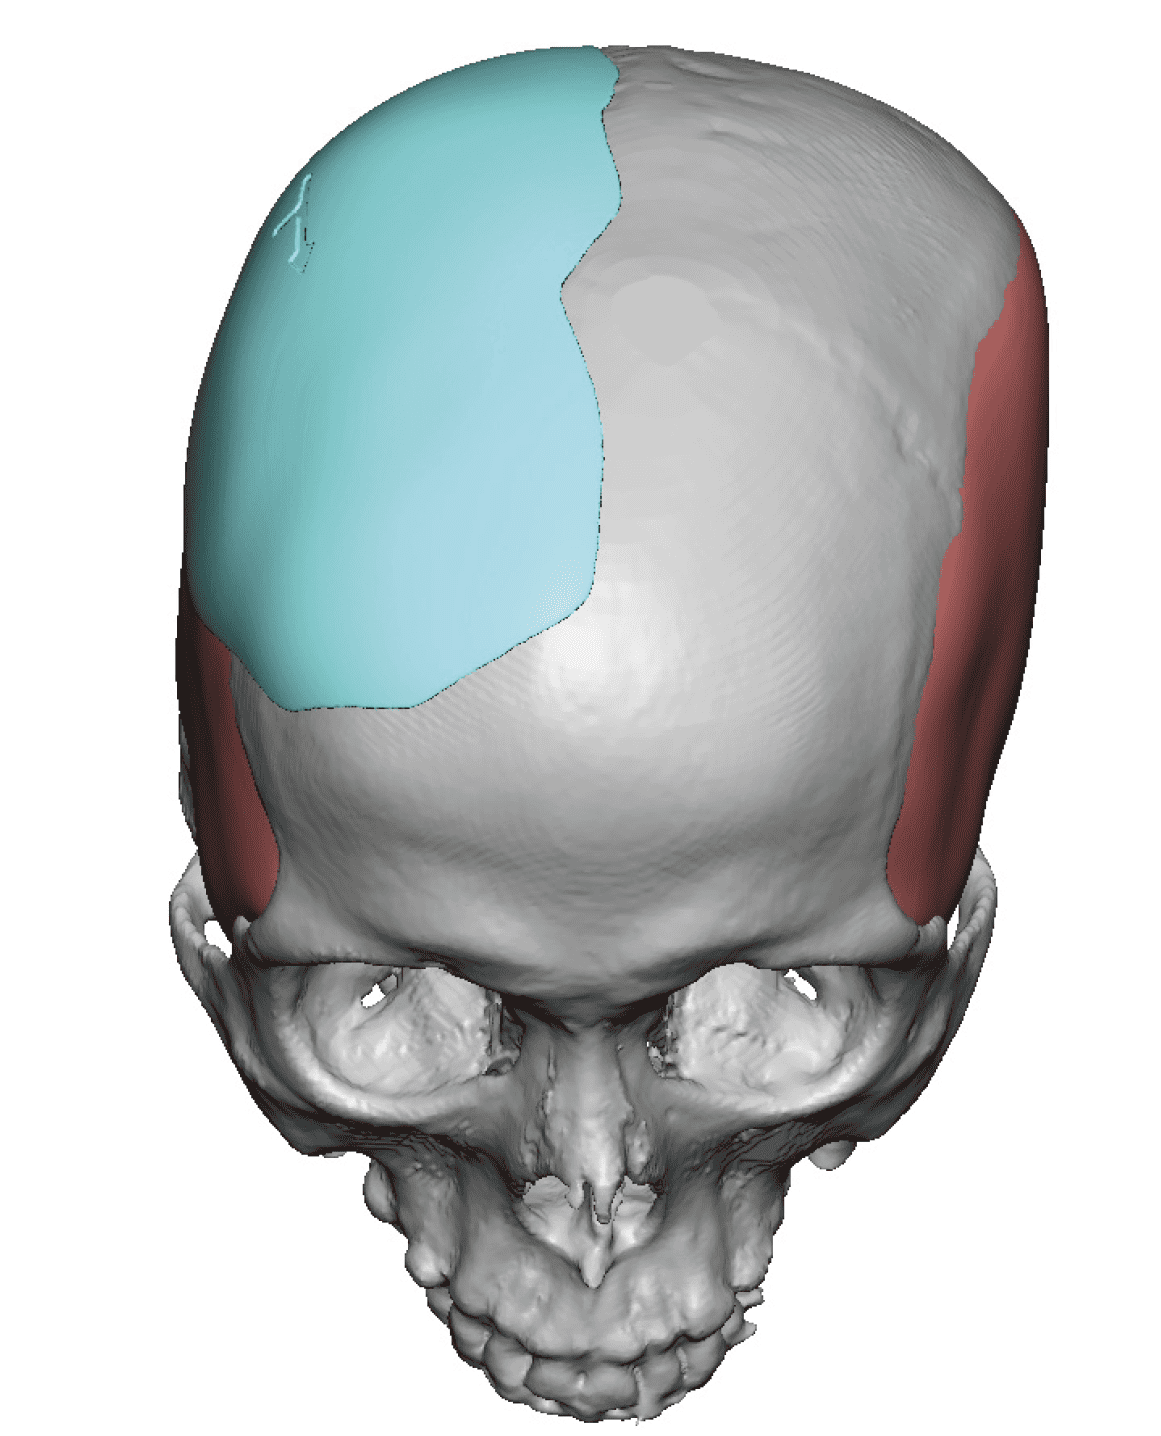

Patient 28

Desire for rounder shape to the top of the head from a congenital parasagittal deficiency skull shape.

Custom skull implant designed to fill in the parasagittal deficiencies.

Desire for rounder shape to the top of the head from a congenital parasagittal deficiency skull shape.

Custom skull implant designed to fill in the parasagittal deficiencies.